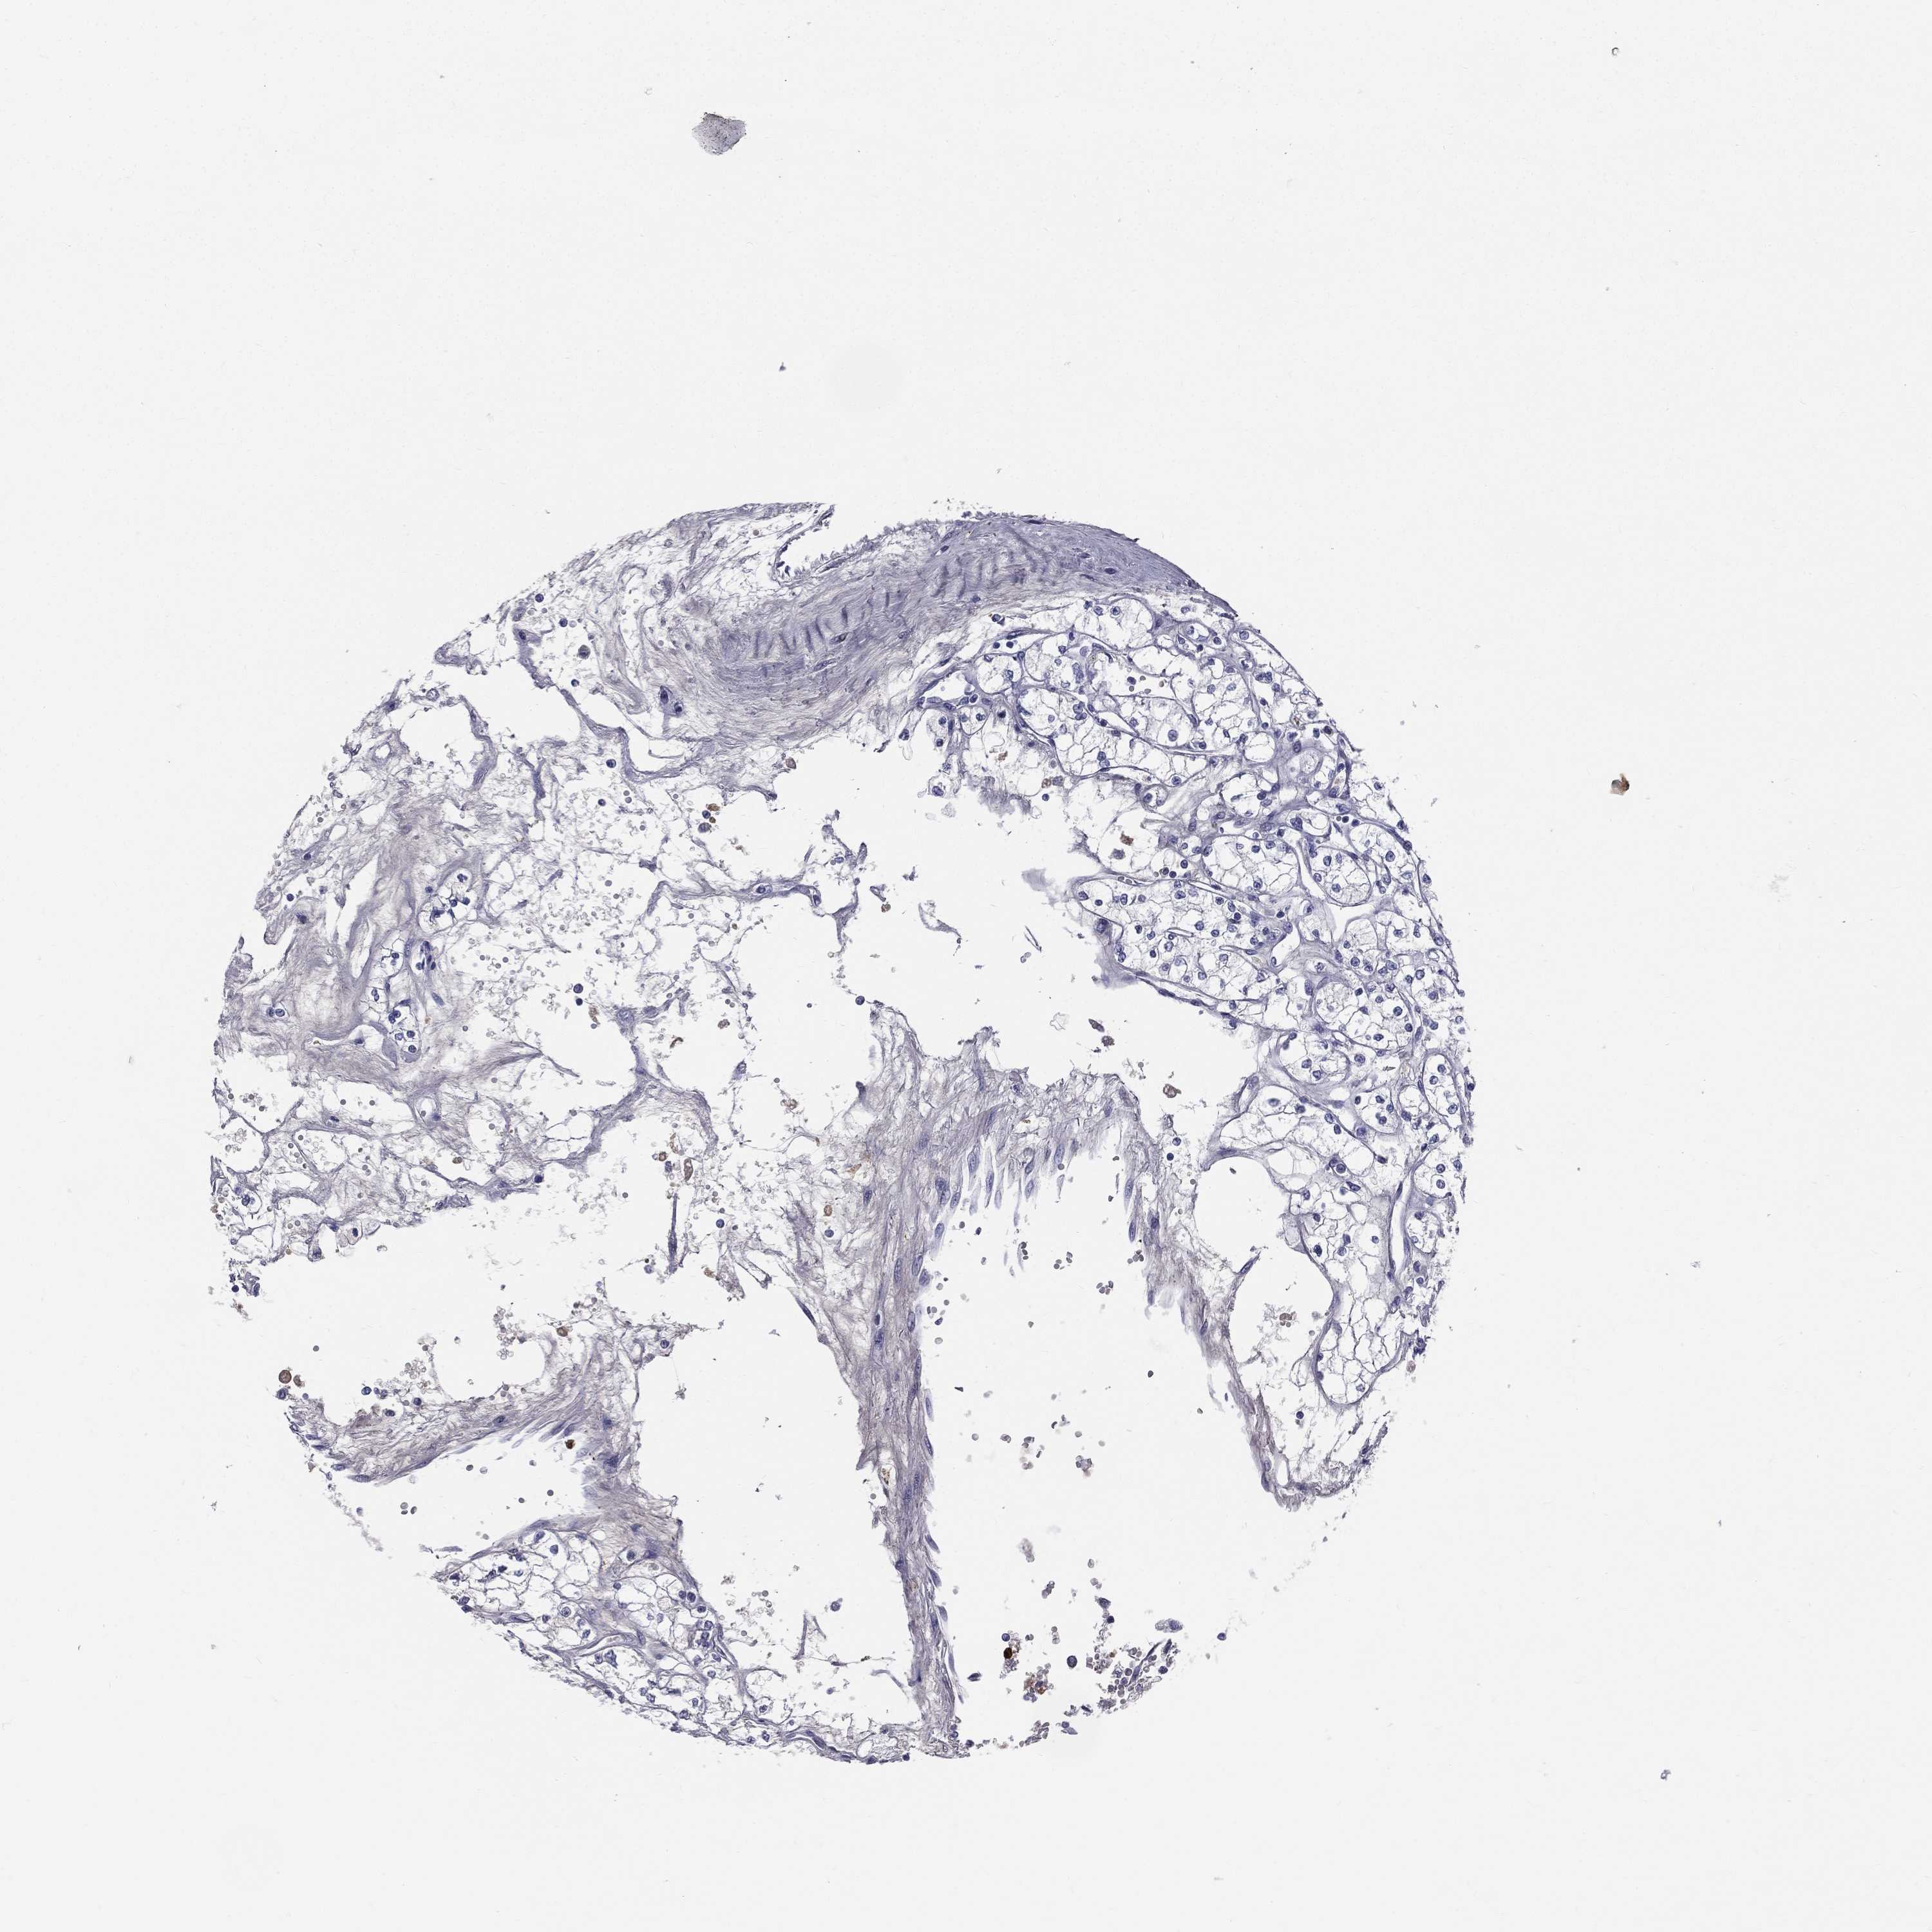

KIDNEY RENAL CLEAR CELL CARCINOMA (VALIDATION) - Interactive survival scatter ploti

The Survival Scatter plot shows the clinical status (i.e. dead or alive) for all individuals in the patient cohort, based on the same data that underlies the corresponding Kaplan-Meier plots. Patients that are alive at last time for follow-up are shown in blue and patients who have died during the study are shown in red.

The x-axis shows the expression levels (FPKM) of the investigated gene in the tumor tissue at the time of diagnosis. The y-axis shows the follow-up time after diagnosis (years). Both axes are complimented with kernel density curves demonstrating the data density over the axes. The top density plot shows the expression levels (FPKM) distribution among dead (red) and alive patients (blue). The right density plot shows the data density of the survived years of dead patients with high and low expression levels respectively, stratified using the cutoff indicated by the vertical dashed line through the Survival Scatter plot. This cutoff is automatically defined based on the FPKM cutoff that minimizes the p-score. The cutoff can be changed by dragging the vertical line or by entering a cutoff value in the square labeled "Current cut-off".

Under the Survival Scatter plot the p-score landscape (black curve; left axis) is shown together with dead median separation (red curve; right axis). Dead median separation is the difference in median mRNA expression between patients who have died with high and low expression, respectively. It is calculated as follows: median FPKM expression of dead patients with high expression - median FPKM expression of dead patients with low expression. This is intended to aid the user in visually exploring custom cutoffs and the associated p-scores and dead median separation.

Individual patient data is displayed and can be filtered by clicking on one or more of the category buttons on the top of the page. Categories describing expression level and patient information include: high, low, alive, dead, female, male and tumor stages. The scale of the x-axis can be toggled between linear and log-scale by clicking on the "x log" button. Mouse-over function shows TCGA ID, patient information and mRNA expression (FPKM) for each patient.

& Survival analysisi

Kaplan-Meier plots summarize results from analysis of correlation between mRNA expression level and patient survival. Patients were divided based on level of expression into one of the two groups "low" (under cut off) or "high" (over cut off). X-axis shows time for survival (years) and y-axis shows the probability of survival, where 1.0 corresponds to 100 percent.

HP is validated prognostic, high expression is unfavorable in Kidney Renal Clear Cell Carcinoma (validation)

Best expression cut offi

Based on the FPKM value of each gene, patients were classified into two groups and association between prognosis (survival) and gene expression (FPKM) was examined. The best expression cut-off refers the FPKM value that yields maximal difference with regard to survival between the two groups at the lowest log-rank P-value. Best expression cut-off was selected based on survival analysis .

When clicking on this number, the vertical dashed line indicating cut-off, the interactive survival plot, and the Kaplan-Meier curve will be adjusted to show results based on the best expression cut-off.

: 5.01

Average pTPM 174.2

Number of samples 100